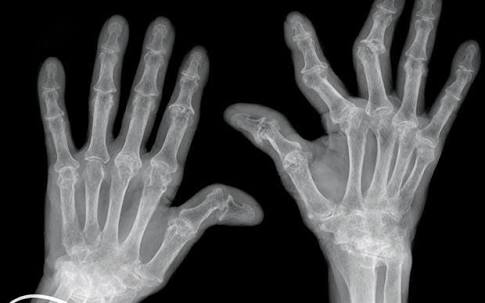

类风湿关节炎,其主要的病理基础是滑膜的改变,当滑膜出现了类风湿滑膜炎改变以后,会逐渐的破坏掉关节腔内的软骨,导致关节间隙的狭窄和关节的粘连,严重的影响患者的生活质量,很多人因为手部的变形甚至筷子都拿不了。

类风湿性关节炎的患者早期通常会表现出明显的晨僵,尤其是表现在手部。很多患者会在早期的时候表现出早上起来的时候,手指的僵硬感,握不拢,而且握拳的时候会有疼痛,通常需要经过30分钟左右的时间才能缓解。

当然当很多患者已经到了晚期,关节已经出现了明显的变形,从相关的查体以及x光片子,也可以明确患者是否存在类风湿性的关节炎。从下图您仔细看就会看出正常的手与类风湿性关节炎手部的骨骼改变。

另外类风湿这种疾病也会导致患者出现比较严重的骨质疏松,建议类风湿患者一定要做双能x线检查,明确自己是否存在骨质疏松,或者说骨质疏松到了什么样的程度,根据结果进行系统的抗骨质疏松治疗。